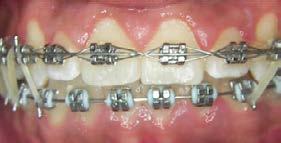

Adherencia a las indicaciones del tratamiento ortodóntico en pacientes con aparatología fija

La adherencia al tratamiento se define como el grado de comportamiento de una persona para seguir las recomendaciones sugeridas por el prestador de servicios de salud, en este caso, el ortodoncista. La adolescencia se considera una etapa idónea para recibir tratamiento de ortodoncia, ya que durante este periodo se presentan cambios fisiológicos, estructurales y anatómicos relacionados con el crecimiento y desarrollo de la cara y de las arcadas dentarias; sin embargo, uno de los principales retos es lograr y mantener una adecuada conexión con el paciente para obtener resultados favorables en la mejora de su oclusión. Objetivo: Evaluar el nivel de adherencia al tratamiento con aparatología fija en pacientes adolescentes del Instituto Bioprogresivo de Ortodoncia. Metodología: Estudio transversal con muestreo por conveniencia. Se evaluó el nivel de adherencia al tratamiento en pacientes atendidos en el Instituto mediante un cuestionario validado de autorreporte, aplicado durante los meses de agosto a diciembre de 2024. Se realizó un análisis descriptivo de la muestra y posteriormente se evaluó la frecuencia de reporte de los ítems. Resultados: El 81.7% de la muestra reportó haber recibido indicaciones higiénicas; el 85.3% recordó las instrucciones dietéticas recibidas; el 96.4% acudió a sus citas en la fecha y hora convenidas; el 97.5% refirió dar seguimiento a su tratamiento, aun cuando ya se sentían satisfechos con los resultados; el 92.6% solicitó consulta inmediata cuando se desprendió algún bracket; el 96.4% siguió las indicaciones incluso al salir de viaje; el 91.5% consultó oportunamente al ortodoncista ante la presencia de alguna molestia; el 92.6% recordó las fechas de sus próximas consultas, y solo el 2.5% reportó haber tenido conflictos con su ortodoncista. Conclusión: La adherencia de los pacientes al tratamiento de ortodoncia en la muestra fue adecuada; no obstante, es importante evaluar de forma constante este aspecto para verificar la motivación del paciente adolescente, evitar la deserción prematura del tratamiento y prevenir posibles complicaciones.

Resultados

En el estudio participaron 82 adolescentes; el 60.9% (n = 50) fueron mujeres, quienes presentaron una edad promedio de 15.3 ± 2.5 años. El 78.1% (n = 64) refirió que era la primera vez que se encontraba bajo tratamiento ortodóntico.

Adherencia al tratamiento

De acuerdo con la encuesta de adherencia en pacientes adolescentes bajo tratamiento ortodóntico, el 81.7% de la muestra reportó haber recibido

indicaciones higiénicas; el 85.3% recordó las instrucciones dietéticas recibidas; el 96.4% acudió a sus citas en la fecha y hora convenidas; el 97.5% refirió dar seguimiento a su tratamiento, aun cuando ya se sentían satisfechos con los resultados; el 92.6% solicitó consulta inmediata cuando se desprendió algún bracket; el 96.4% siguió las indicaciones incluso cuando salieron de viaje; el 91.5% consultó de manera oportuna al ortodoncista ante la presencia de alguna molestia; el 92.6% recordó las fechas de sus próximas consultas y solo el 2.5% reportó haber tenido conflictos con su ortodoncista (Tabla 2).